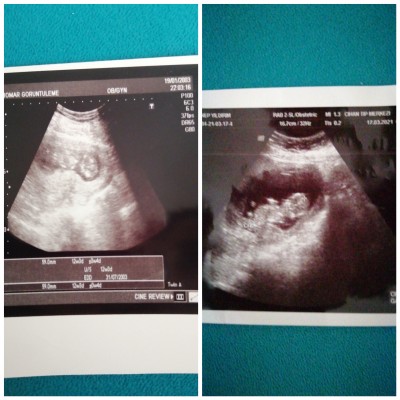

Erkek hissediyorum ama cinsiyet tahmini yapicak arkadaşlar varsa çok sevinirim

Gebelik haftası 12+3 hafta

Canım banada erkek gibi geldi 20+0 bugün benim oğlanın ultrason resmi gibi aynı hayırlısı olsun sağlıklı olsun inşaallah ❤️

Soldaki kızı dı Bu ada erkek dediler ama burda sureklı yorum okumaktan pıskolojım de bozuldu görduğümede süphe duyar oldum

şebek yaa bacaklarını nasıl açmış erkek bu erkek :) bende 12+3 te öğrendim kızım olacak allahın izniyle gerçeği doktor tahmin söyledi :)